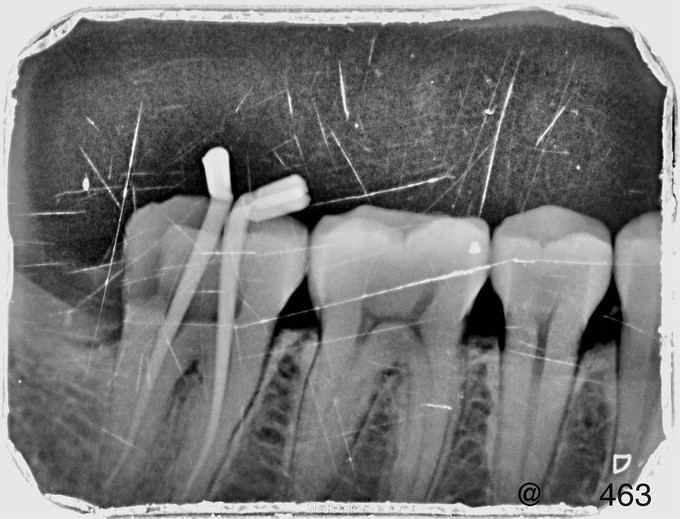

临床检查:48未完全萌出,盲袋附着无溢脓,47合面无明显龋坏,远中邻面探(++),冷(++),叩(-),松动度(-),牙周正常. 辅助检查:X线示48近中阻生,47龋坏累积髓腔,根尖周牙周膜增宽。

诊断:47牙髓炎,48阻生齿。 治疗:经患者知情同意后,47局麻去腐降牙合,开髓拔髓寻找根管口,建立直线通路,扩通根管,确定工作长度。S3/EDTA凝胶镍钛器械,低浓度次氯酸钠冲洗根管,预备至25/06,氢氧化钙诊间封药,48翻瓣拔除,缝合。一周后复诊,试主尖X线示恰充,试干根管,导AH-PLUS糊剂,热压胶垂直加压根充,术后见根管恰充,暂封观察嵌体修复。拔牙创拆线。